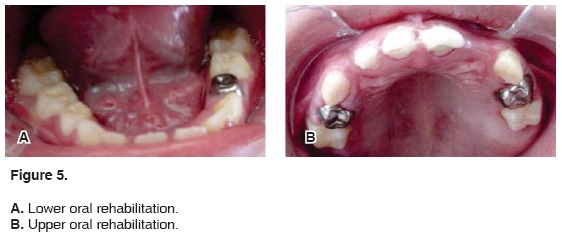

First session: Mandibulartopic and regional anesthesia was used with total isolation. Treated teeth were number 85 and 84. Teeth were treated with resin and pit and fissure sealers, tooth number 46 was treated with pit and fissure sealer (Figure 5A).

Second session: The patient was subjected to mandibular local anesthesia. The following procedures were performed: tooth 74 received a steel-chrome crown, tooth 75 received resin and pit and fissure sealant, tooth 36 received pits and fissure sealant (Figure 5A).

Third session: Topical anesthesia was administered to then proceed to infiltrative anesthesia. The area was completely isolated and the following treatments were performed: Tooth 53 received resin restoration, tooth 54 received a steel-chrome crown, tooth 55 received resin restoration (Figure 5B).

Fourth session: After using topical anesthesia, the anterior-superior area was infiltrated and isolated with cotton rolls. Treated teeth were 51, 52, and 61. These teeth were about to exfoliate, were already mobile and presented root resorption. Treatment consisted of carious tissue removal, teeth reconstruction with Glass Ionomer Cement and observation (Figure 5B).

Fifth session: Topical anesthesia was first used to then proceed with infiltrative anesthesia. The upper left quadrant was anesthetized. Total isolation was observed, rehabilitation was performed in the following fashion: Tooth 63 received resin restoration, tooth 64 received a pulpotomy and chrome-steel crown and tooth 65 received a resin restoration (Figure 5B).